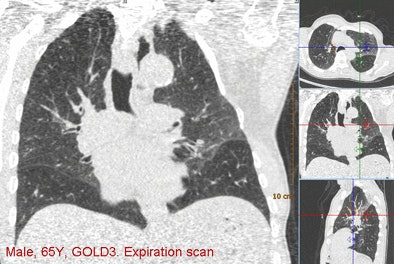

| Above, images from the expiration scan of a 65-year-old man with GOLD stage 3. The image shows increased density in some areas, common in expiration scans, but also regions that remain dark and are indicative of air trapping. Below, the overlay images from a single coronal section show that the left upper lobe is normal, while two lobes had emphysema and two had air trapping, indicating mixed-phenotype COPD. |